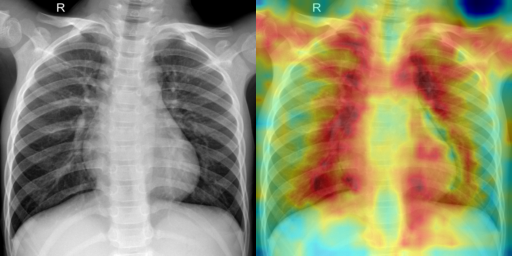

a) Chest X-Ray (Pneumonia) Dataset. We compare a baseline PatchCore system (memory from the full training set, no IL) against our proposed IL strategy using the Chest X-Ray dataset, which begins with 30% seed normal samples. Evaluation is performed on a held-out test set with mixed labels. As shown in Table 1, IL substantially improves performance across multiple metrics. ROC-AUC increases from 0.6834 (baseline) to 0.8968, while PR-AUC improves from 0.7656 to 0.9372. Accuracy also rises from 0.6538 to 0.8093. Precision improves from 0.7620 to 0.8796, with recall increasing from 0.6487 to 0.8051, resulting in an F1 gain from 0.7008 to 0.8407. In addition to these improvements, false positives are reduced from 79 to 43 while true positives increase from 253 to 314. Fig. 2 illustrates the heatmap of the baseline and proposed method, which shows the proposed method focusing better on the important regions. We depicted the baseline and proposed methods’ PR and ROC curves in Fig. 3. For a clearer illustration of the number of correctly predicted samples compared to baseline, we present the confusion matrices in Fig. 4.